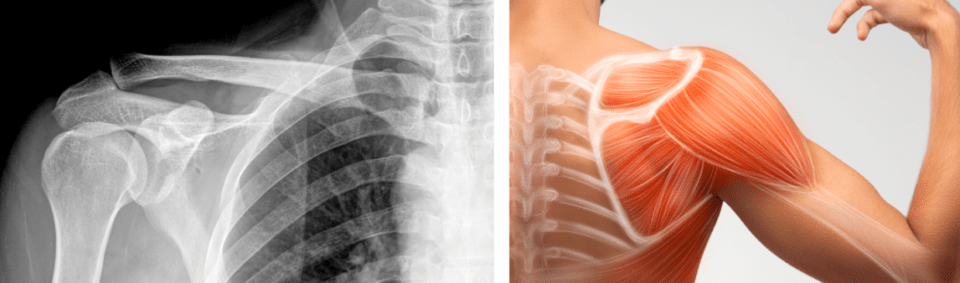

La Paz, 13 de ene 2026 (ATB Digital) .- El traumatólogo Abraham Sulcata explicó que la calcificación es la acumulación de cristales de calcio en los tendones del hombro, provocando un dolor agudo en la zona. Esta afección, según Sulcata, aparece por la mala postura o realizar movimientos repetitivos que afecten directamente a los hombros.

Sin embargo, esta afección sí tiene solución; el médico recomienda realizar elongaciones antes de los ejercicios físicos, mejorar la postura y recuerda que “no se debe acostumbrarse al dolor”, sino acudir de inmediato a un centro de salud para una evaluación e iniciar un tratamiento.